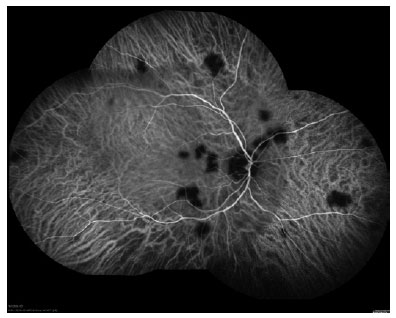

The ophthalmic assessment revealed visual acuity of 20/20 in the right eye (OD) and light perception in the OS. OS examination showed perforation and iris tamponade. Biomicroscopy and intraocular pressure were unremarkable in the OD. The fundoscopic examination was impossible in the OS, and there was multifocal choroiditis in the OD. Fundus photography showed multiple yellowish rounded lesions in the OD. Fluorescein angiography revealed multiple hypofluorescent lesions in the early phase and hyperfluorescent lesions in the late phase. Indocyanine green angiography (ICG) revealed rounded well-defined hypofluorescent lesions in the posterior pole and mid-periphery, indicating multifocal choroiditis (Figure 1).

ICG is a cyanine dye that has ideal infrared frequencies to penetrate the retinal layers, allowing ICG angiography to image deeper circulation patterns than fluorescein angiography. Its importance is related to the detection of subclinical choroidal lesions and their follow-up(5). In this case report, ICG angiography revealed more lesions than was observed during fundus examination, and it was useful to assess choroiditis recovery. In conclusion, ICG the exam showed a different pattern of choroiditis related to sporotrichosis from those previously described.